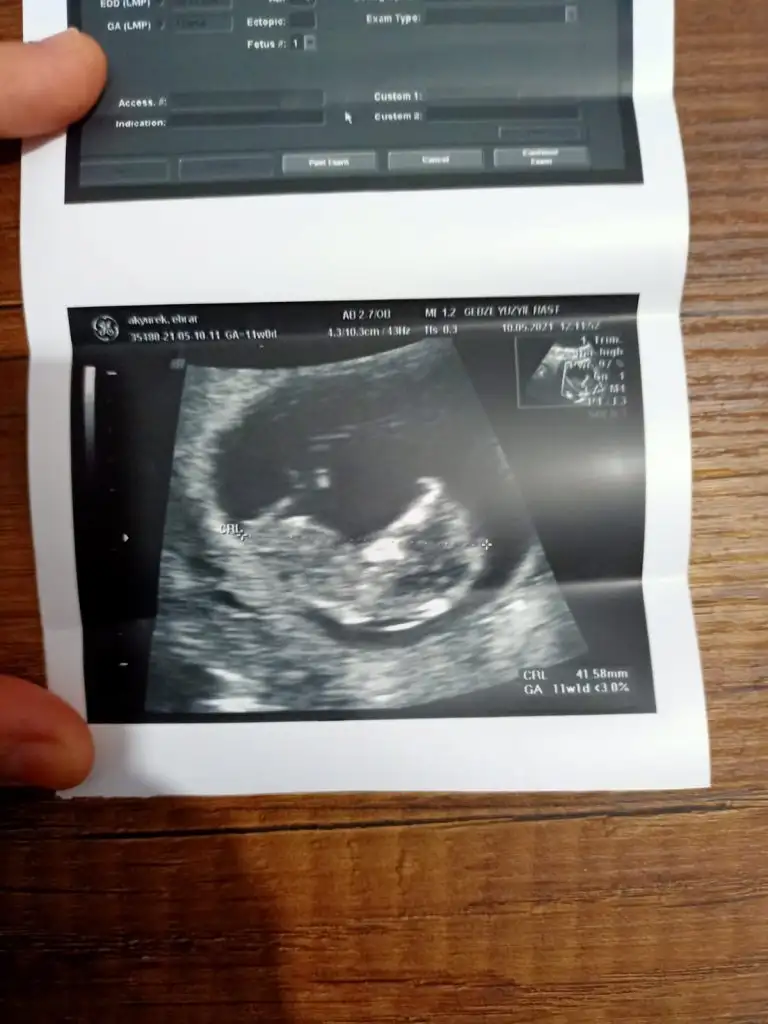

Emin olmadım ama sanki kız gibi geldi banaMerhaba arkadaslar,aslinda bebegimin cinsiyeti belli,dr.eşime kağıda yazıp verdi ama eşim pazar gunu surpriz yapacagi icin bana søylemiyor,sizin bi tahmininiz varmı?Merakdan çatliyorum.Eki Görüntüle 2848569

Valla bravo arkadaşım,az ønce øgrendim, Allahin izniyle zillim geliyorEmin olmadım ama sanki kız gibi geldi banaen iyi 11 12 13 haftalar olmalı yada başka USG varsa paylaşın

Anketimi oylarsaniz sevinirim sağlıkla gelsin prensesIkra hanım merhaba 11+1den karından usg atıyorum rica etsem tahminde bulunur musunuz arkadaşım için bana kız demiştiniz doğru cıktı

Erkek görünüyorIkra hanım merhaba 11+1den karından usg atıyorum rica etsem tahminde bulunur musunuz arkadaşım için bana kız demiştiniz doğru cıktı

Kız diyecem ama emin olamadım

Bir de benimkine baksanız olur muEmin olmadım ama sanki kız gibi geldi banaen iyi 11 12 13 haftalar olmalı yada başka USG varsa paylaşın